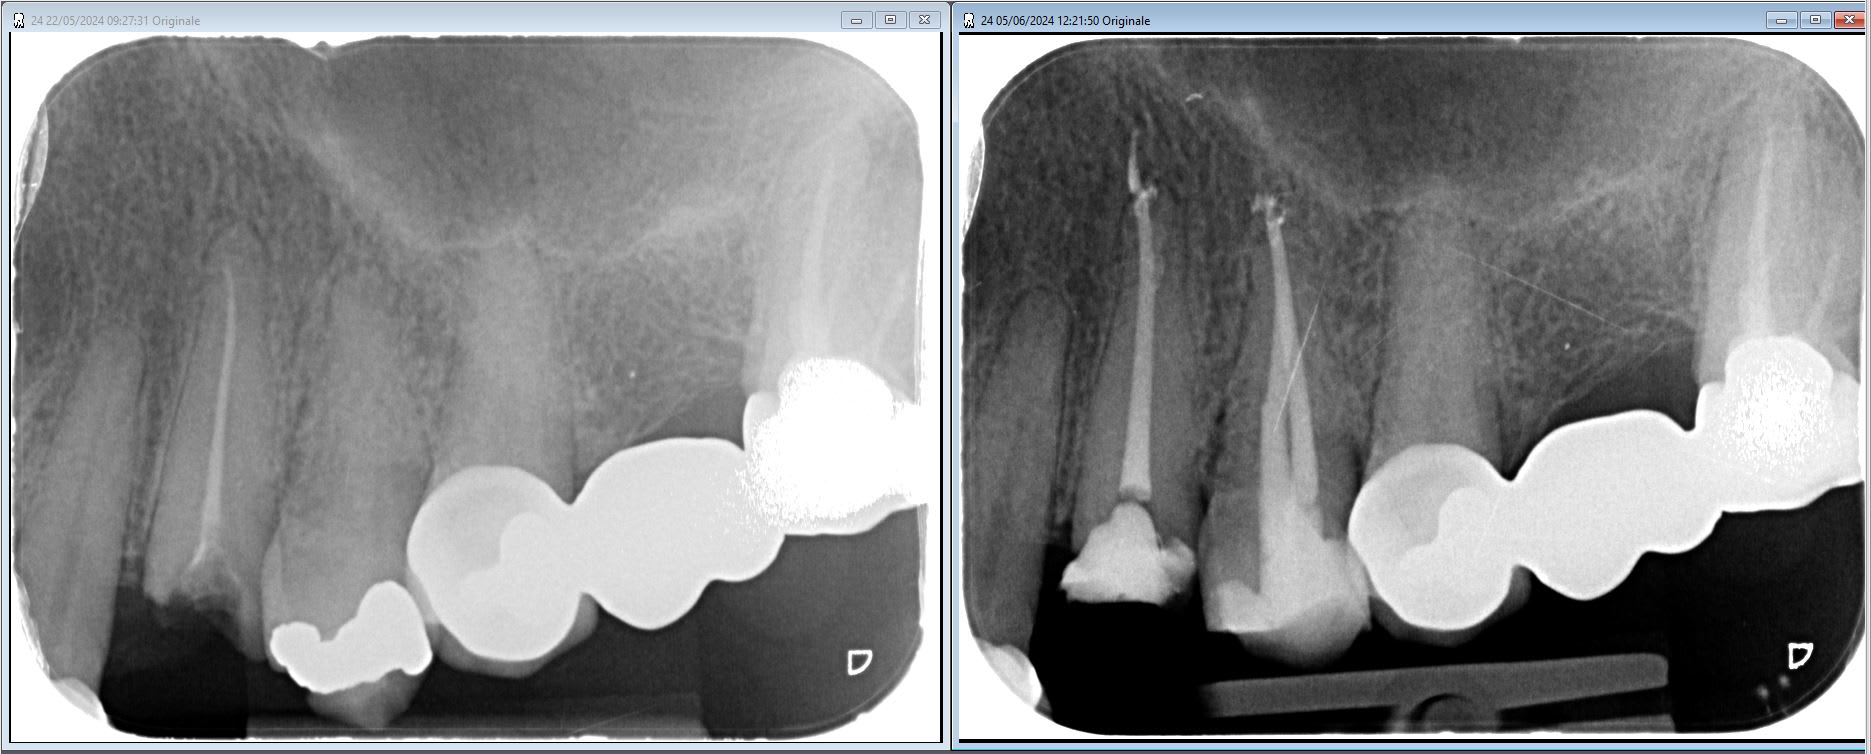

Re RIMPP.

Vdta6j3grpvckkb08kwklt4fqxa1 - Eugenol

bin la par exemple la 4 elle aura droit a son IC des familles... mais c'est rare, et y'aura un ic car flemme de faire une RIMMP... trop chronophage de bien isoler, hors tarif rac0 pourquoi pas.

La 4 ne sera pas en RAC0, mais en NR, enfin en cas de contrôle sécu c'est pas justifiable.

la 4 en mesial je suis quand meme assez bas...

Richmond ou ic/cr, NR en théorie, au vu de la radio.